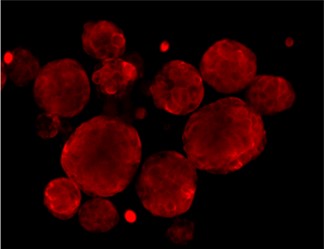

Immunofluorescence staining of Src and Phospho-Src

SRC total

DAPI